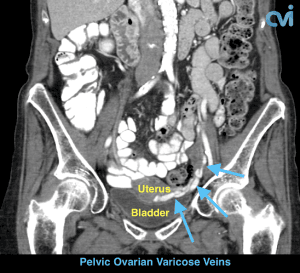

Pelvic Congestion Syndrome (PCS) or Pelvic Venous Congestion Syndrome (PVCS) is essentially varicose veins of the ovaries. Varicose veins are most commonly seen in the legs and are caused by the veins becoming less elastic resulting in abnormal flow of blood causing it to pool in certain areas, leading to enlarged painful veins. This is also what happens to the pelvic veins in pelvic congestion syndrome.

PCS most commonly occurs in young women, and usually in women who have had at least 2-3 children. During pregnancy the ovarian vein can be compressed by womb or increase in size because of the required increased blood flow. This is thought to damage the valves causing them to stop working resulting in abnormal blood flow backwards. This pressure build up causes the pain of PCS and may also cause visible varicose veins around the vulva, vagina, inner thigh, sometimes the buttock and down the leg(s). painful veins. This is also what happens to the pelvic veins in pelvic congestion syndrome.

The abnormal veins dilate and cause varicose veins around the ovary and uterus because the valves don’t work properly. Blood flow is in the wrong direction, pooling in the veins and causing them to enlarge.

PCS can be diagnosed by Ultrasound or CT of the Abdomen and Pelvis.

Magnetic resonance imaging (MRI) and computed tomography (CT) is another method to diagnose pelvic congestion syndrome. Our practice requires a CT of the Abdomen and Pelvis with contrast prior to treatment. This allows us to see where the varicose veins are coming from so that we can plan and do the appropriate treatment. Sometimes there are abnormal pelvic veins in addition to the ovarian veins that need treatment. Sometimes PCS can be missed on CT if the contrast injection is not timed appropriately or the vein is not directly measured.